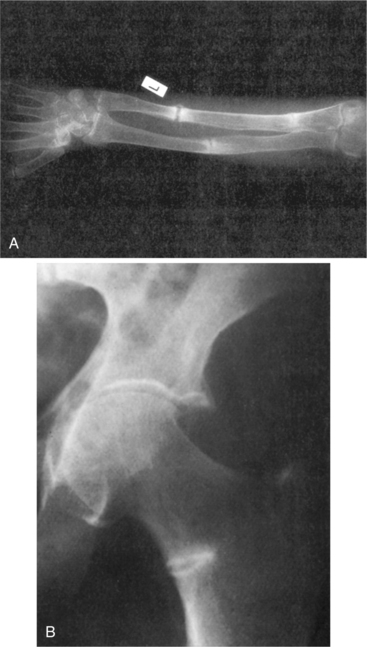

Demineralization results in an exaggeration of the osteoid seams seen radiographically adjacent to the relatively sparse areas of calcified bone (Fig. 24-6). As the osteoid accumulates, bone strength declines. These exaggerated seams occur because of the excessive time lag between collagen deposition and the appearance of the calcium salt. Areas of abundant osteoid appear radiographically as radiolucent stripes. These so-called pseudofractures, known as Looser’s zones, occur most commonly on the concave side of long bones, the ischial and pubic rami, and the ribs and scapula (Fig. 24-7). These pseudofractures develop from the healing of multiple microstress fractures in the moderately severe form of osteomalacia sometimes referred to as Milkman’s syndrome.107

Figure 24-7 Osteomalacia. A, Forearm and B, femoral neck. Looser zones are seen as translucent zones with sclerotic margins. Usual sites include the medial femoral neck, pubic rami, lateral borders of the scapulae, and ribs. Complete fractures can extend through Looser’s zones; these will heal with appropriate treatment. (From Bullough P: Orthopaedic pathology, ed 3, London, 1997, Mosby-Wolfe.)

Radiographically, osteomalacia, like osteoporosis, may present as osteopenia. A bone biopsy may be done at the site of osteopenia to evaluate the bone matrix. Besides osteopenia, radiolucent bands in the bone cortex (Looser’s zones) may be revealed radiographically (see Fig. 24-7).